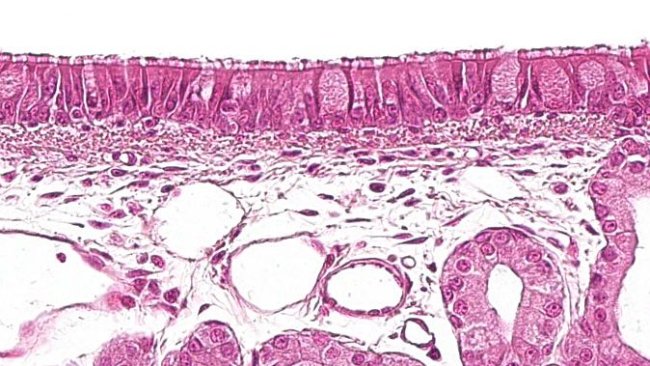

Cet article décrit les principales lésions qui caractérisent les principales pneumonies bactériennes. Bien que la plupart soient des agents opportunistes, il existe deux agents bactériens primaires qui sont capables de causer des lésions par eux-mêmes.

Quels types de cellules composent le système de défense respiratoire chez les porcs ? Comment s'organisent-elles et communiquent-elles entre elles ?

Cet article analyse les différentes lésions micro et macroscopiques causées par le virus du SDRP, le PCV2, le virus de la grippe porcine et le coronavirus respiratoire porcin.